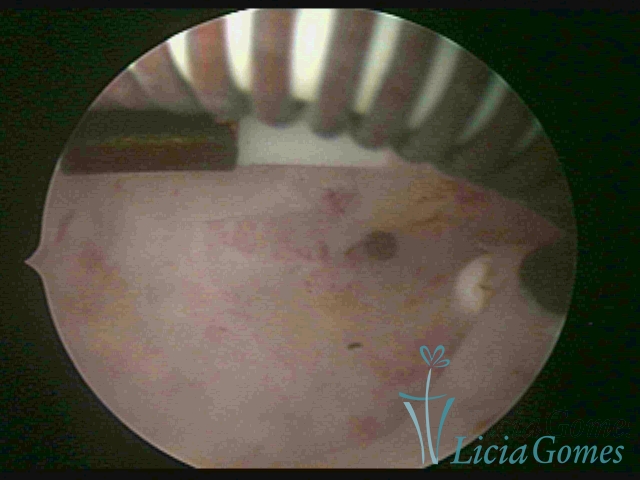

Canal cervical com fio do DIU